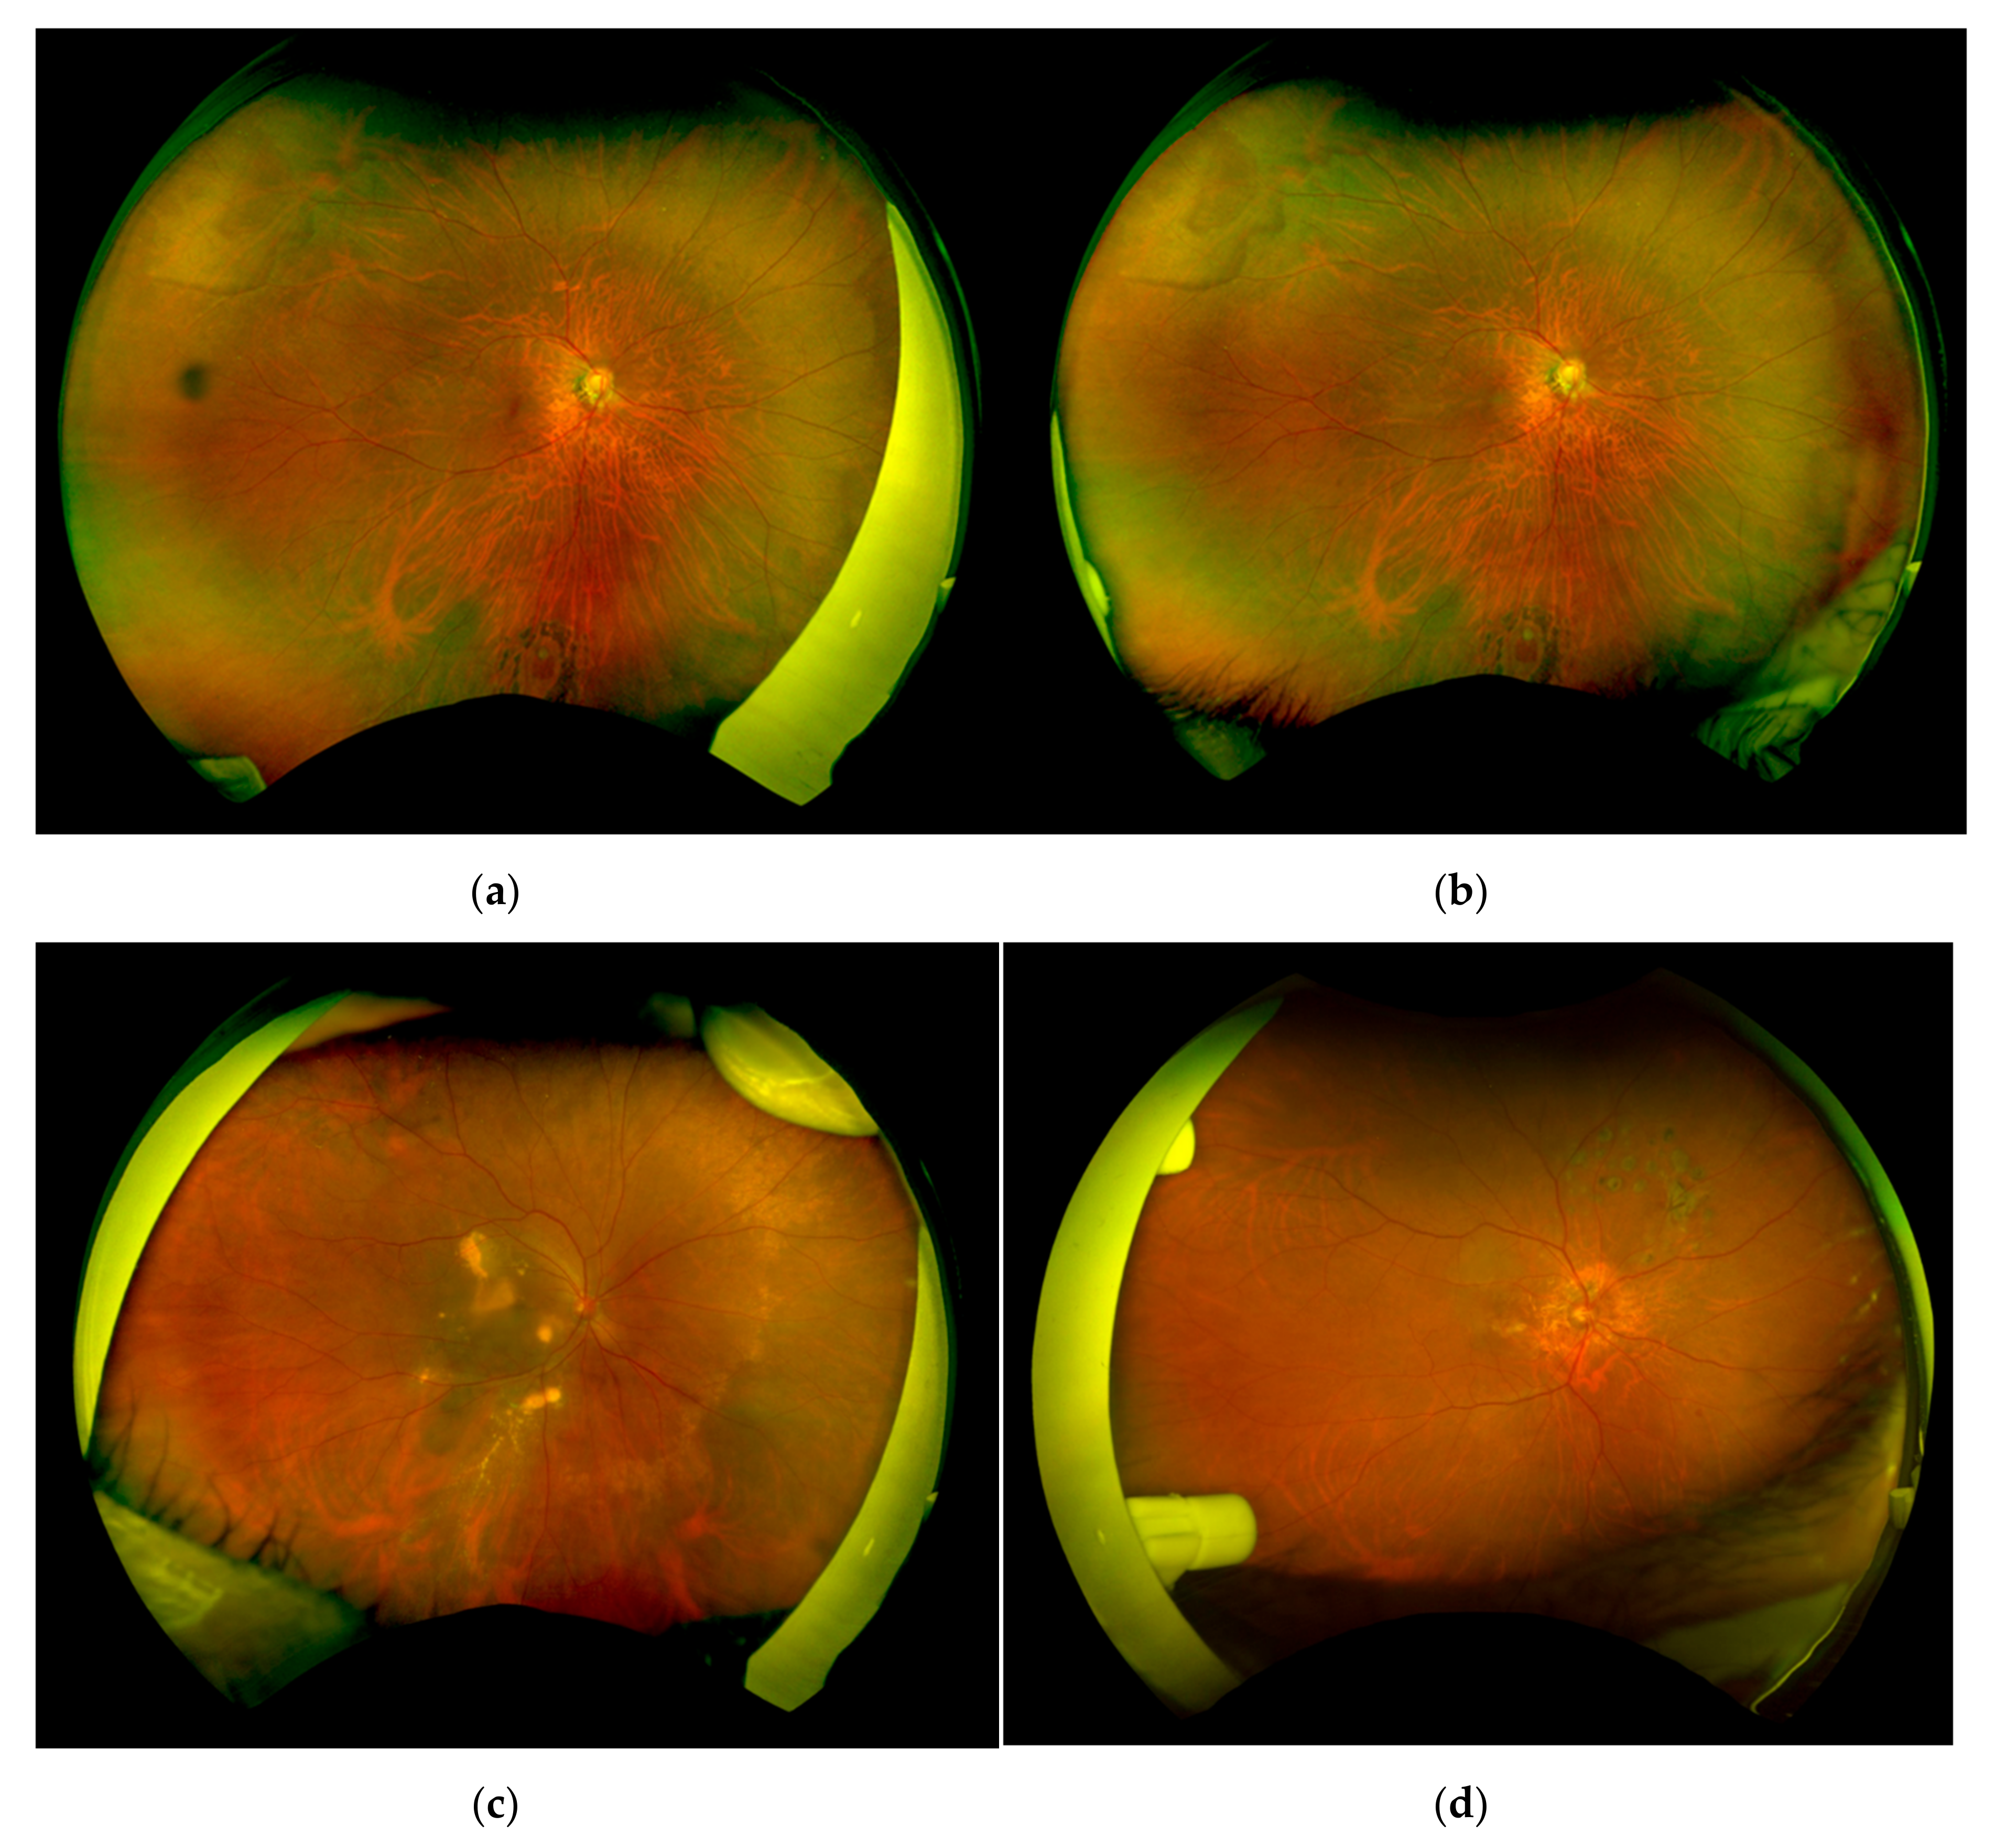

The ultra-widefield fundus imaging was successfully performed with both conventional tape fixation and the eyelid clamper (Figure 3). The average age of the patients was 67.9 ± 10.6 years old, 17 patients had phakic eyes, 13 patients had cataracts, and 2 patients had intraocular lens. The average refraction (spherical equivalent) was −3.13 ± 4.75 diopters. The main diseases of the patients were age-related macular degeneration (7), retinal vascular occlusion (4), diabetic retinopathy (3), retinal tear (1), viral retinitis (1), and inherited retinal degeneration (1).

The average number of pixels in the total areas of the conventional tape fixation and the eyelid clamper were 4.32 ± 0.34 and 4.31 ± 0.35 mega pixels, respectively (Figure 4a). There was no significant difference between the two groups (p = 0.889). In the nasal quadrants, the average area of the visible retina in the eyelid clamper group was significantly larger than the eyelid clamper group (p = 0.0003, Figure 4b). On the other hand, the average area was significantly larger in the tape group compared to the eyelid clamper group in the temporal quadrants (p = 0.0087, Figure 4c). There was no significant difference in superior and inferior quadrants (Figure 4d,e).

In this study, we evaluated the efficiency of the newly invented eyelid clamper and found that the average area of the visible retina was almost equal between the conventional tape fixation group and the eyelid clamper group. In some cases, with the eyelid clamper, an obstruction by the nasal part of the plastic ring was seen in the temporal area of the fundus image (Figure 3d) which might result in smaller visible retinal images in the temporal quadrant (Figure 4c). On the other hand, the tape group showed significantly smaller visible retinal images in the nasal quadrant, partly because examiners had to support the eyelid to open with their fingers from the temporal side of the patient, even with tape fixation (Figure 3d).

Figure 3. Ultra-widefield fundus photographs. Representative retinal images with a tape fixation (a) and the eyelid clamper (b). Representative images obstructed by examiner’s finger to support insufficient fixation with tape (c), or parts of the eyelid clamper (d).